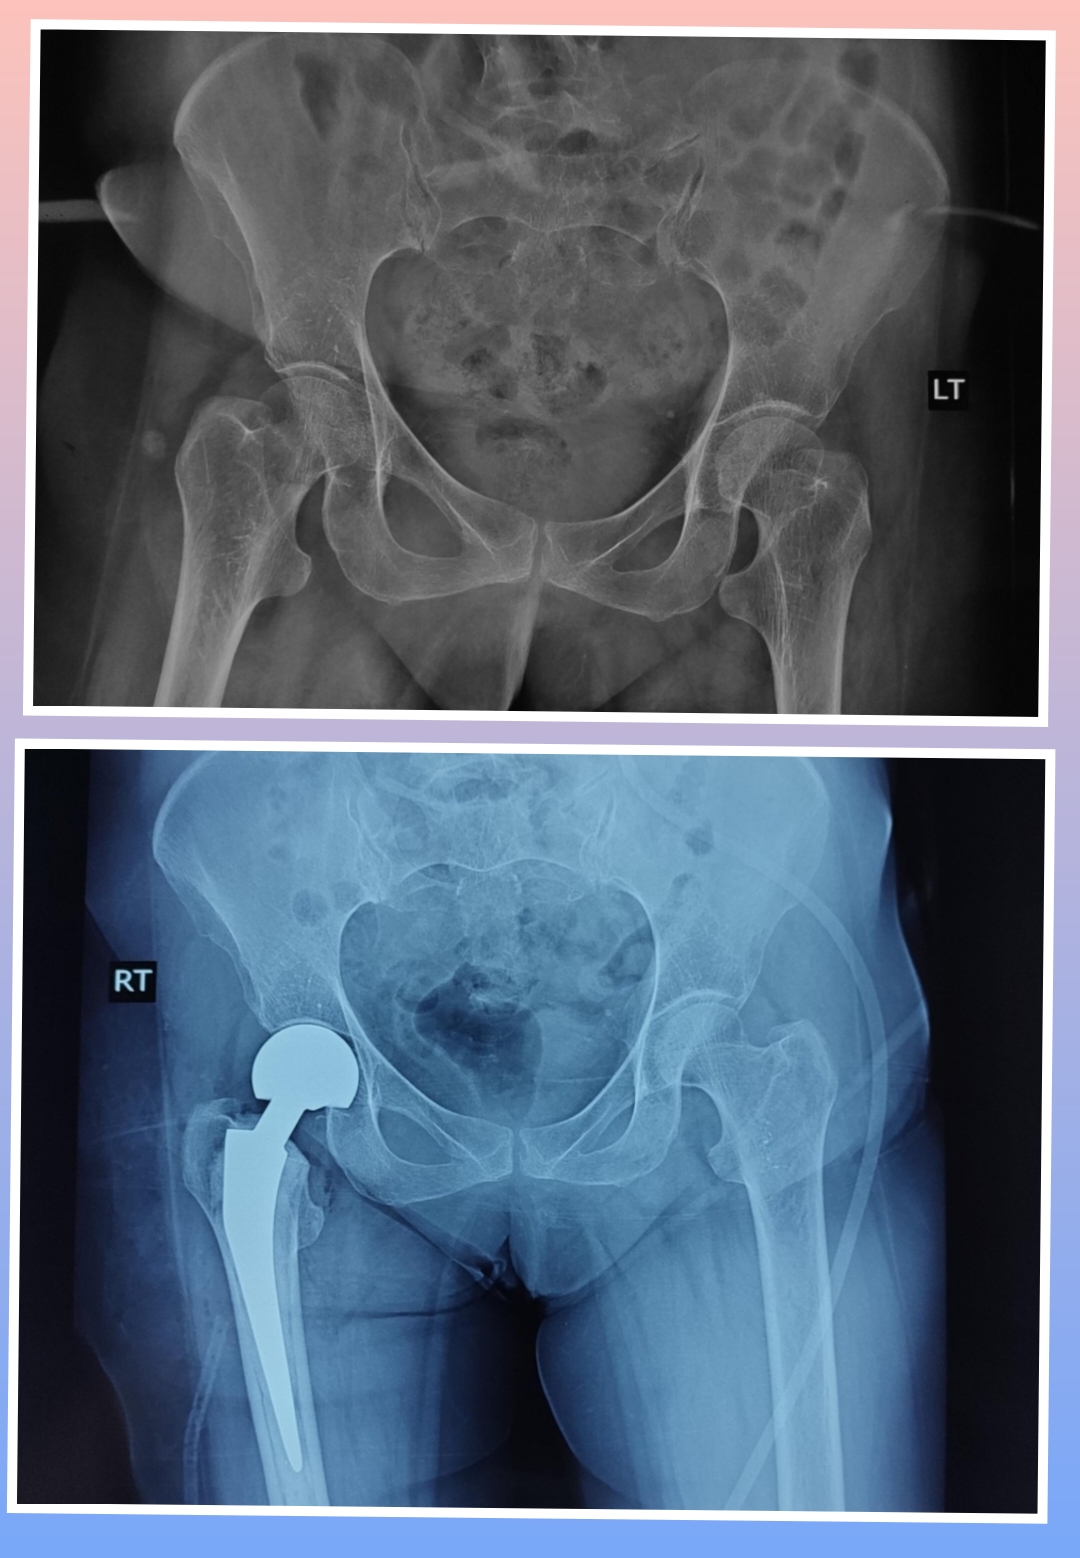

X-ray

Surgeries